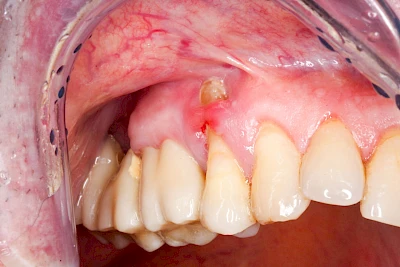

Bei einer Fistel hat sich meist eine Entzündung (manchmal auch Erreger selbst) z. B. aufgrund von Karies oder aufgrund eines Unfalls über den Zahnnerv und die Wurzelspitze (Apex) in den umliegenden Knochen ausgebreitet (apikale Parodontitis) und schnell einen Weg durch den umgebenden Knochen und die aufliegende Schleimhaut in die Mundhöhle gebahnt.

Fisteln sind in der Regel nicht schmerzhaft und fallen häufig als kleine Öffnung weiter entfernt vom Zahnfleisch nahe der Umschlagfalte auf. Aus der Fistelöffnung entleert sich spontan gelbliches Sekret (Eiter) oder es lässt sich mit dem Finger ausstreichen. Manchmal beschreiben die betroffenen Menschen immer wieder einen komischen Geschmack im Mund.

Im fortgeschrittenen Stadium kann die Schleimhaut sich weiter zurückgezogen haben und die Wurzelspitze sichtbar sein. In der Regel treten bei Fisteln keine Schwellungen auf, weil sich die Entzündung nicht im Gewebe ausbreitet.